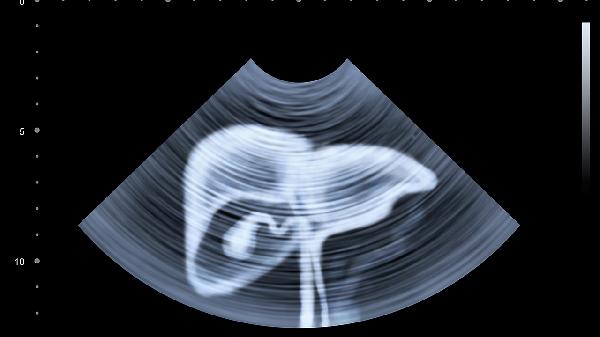

2、B超检查不可少

肝功能正常的脂肪肝患者,往往只有通过B超才能发现。35岁以上人群,最好每2年做一次腹部超声。